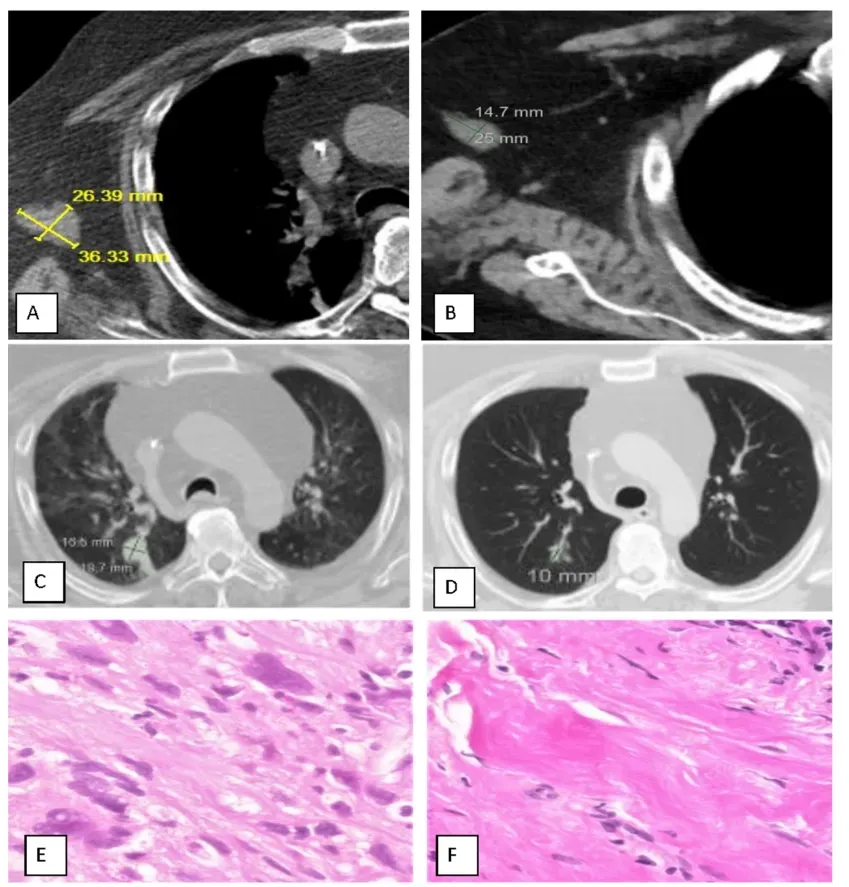

图2 经MITI成功治疗的转移性纤维肉瘤患者病例

注:(A、C、E)治疗前;(B、D、F)治疗后。CT扫描:左臂残端肿块。(A):36.3 × 26.4 mm = 958.2 mm²(异常;全部为癌);(B):25 × 14.7 mm = 367 mm²(显著缩小;活检证实癌组织完全消失,见下方F)。CT扫描:肺右下叶肿块。(C):19.7 × 15.5 mm = 305.4 mm²(异常);(D):10 × 8 mm = 80 mm²(正常)(显著缩小;癌组织完全消失)。活检组织病理:左臂残端。(E):癌:黏液样纤维肉瘤;(F):良性纤维性假瘤。

Abscopal 31%:4例远端转移自己消失

与图2C–D(肺转移灶前后对比)对应

13例中4例出现非注射部位客观缓解,发生率31%。细节如下:肉瘤患者右下肺结节19.7×15.5 mm → 10×8 mm,活检转阴;膀胱癌患者双肺+肝转移灶PET完全阴性,肝穿刺未见癌;宫颈癌阴道残端结节消退60%;脊索瘤大腿皮下多灶结节融合径下降72%。

Pseudoresiduum 57%:影像会撒谎,病理才拍板

与图2E–F(活检对照)对应

7例接受治疗后穿刺,4例CT上仍见>1 cm强化灶,但组织学仅见纤维假瘤,无活癌;该比例占穿刺人群的57%,占全组31%。作者据此修正iRECIST,把“病理阴性”直接定义为iCR或iPR,防止过度治疗。他们提醒,免疫+消融后血管正常化可造成持续强化,PET-CT亦可能因炎性摄取假阳性,因此“能穿就穿”应成为瘤内免疫试验的标配终点。